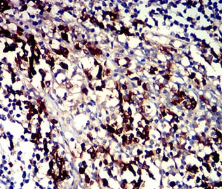

IHC    1/200 - 1/1000